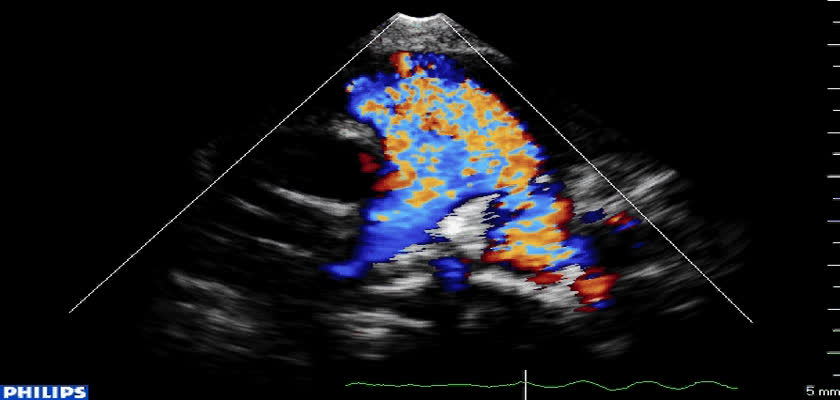

先天性心脏病超声诊断-先天性心脏病超声诊断视频133